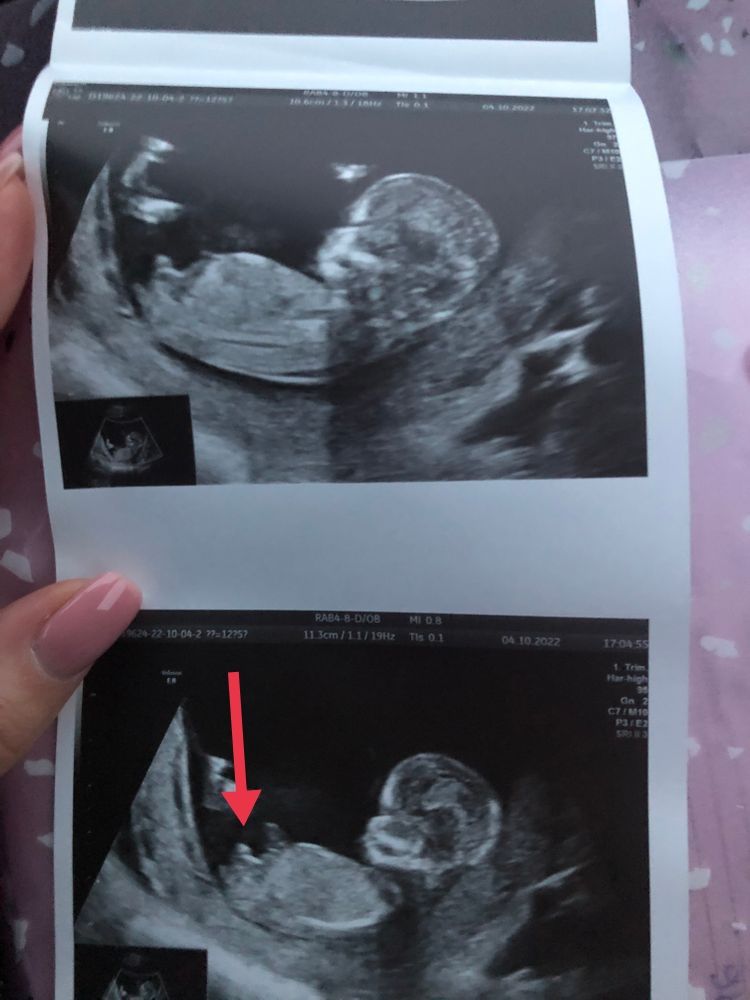

не могу определить по фото где именно половые бугоки,а где ноги или что-то другое 😅на нижнем фото -как будто вообще 3 штуки )

Kseni, В принципе Вам врач намекнула уже😉. Да и на снимке видно что Мальчик. Плюс она сказала 3 бугорка. У девочки сами понимаете не может быть трёх бугорков😁

Kseni, по первой которую Вы скинули в комменты тоже похоже что парень. Не мне говорили иначе. "У Вас бугорков нет всё прямое девочка". А Вам прям акцент на эти бугорки сделали. Прям уверена я что пацан.

Вера

Я тоже не могу понять где именно тот бугорок))) но они все кверху,а значит- там скорей всего мальчик)

Kseni, может быть часть ноги. Но то что я указала это точно половой бугорок. У сына такой же был